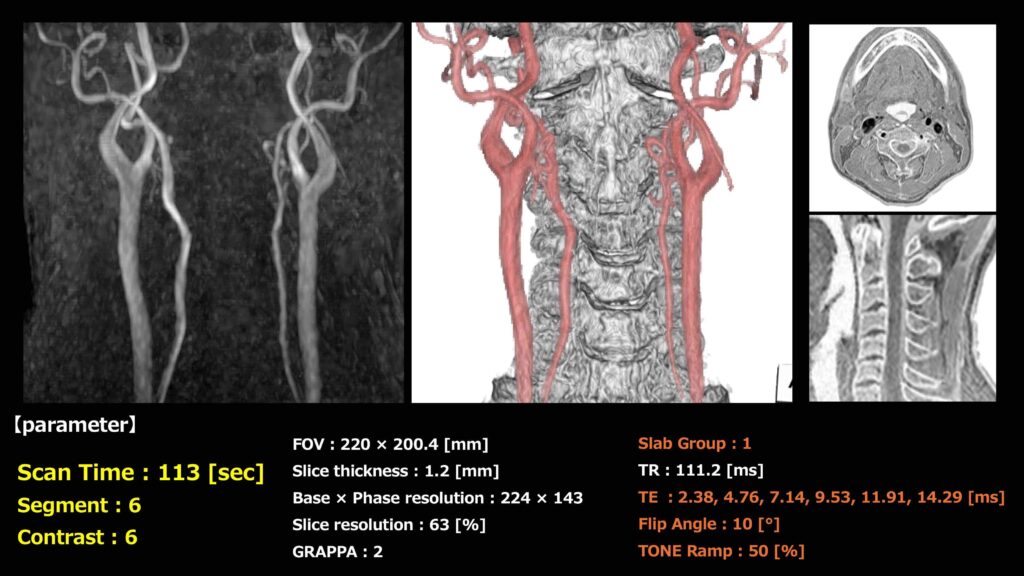

本法で取得した健常ボランティアの画像とパラメータをFig.3に示します。本法では、113秒という短時間でMRA(MIP)、VR、Bone imageの同時取得が可能です。さらに、6つのTEの中から最適な画像を選択してMIPを作成できるため、流速依存による描出不良を回避できると考えています。また、同一シーケンスで画像を取得するため、VRで位置ずれが生じないという利点もあります。